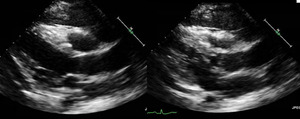

Complete blood count revealed white blood cell count 73,000 cells x 109/L with 88% blast cells, hemoglobin 10.5 g/dL, and platelets 23,000 x 109/L. Lactate dehydrogenase (LDH) 1355 IU/L and uric acid 6.2 mg/dL. ECG showed sinus tachycardia with heart rate of 109 beats per minute, poor R wave progression, and no ischemic changes. A CT scan of the chest, abdomen, and pelvis revealed an extensive anterior mediastinal mass with mediastinal lymphadenopathy, a small pericardial effusion, and large left-sided pleural effusion with pleural thickening (Figure 1). An echocardiogram showed normal left ventricular size with hyperdynamic function, mild pulmonary hypertension, elevated right-sided filling pressures, and bilateral pleural effusions. A large pericardial effusion was visualized, along with pericardial thickening. There was echocardiographic evidence of tamponade physiology with significant respirophasic variation of mitral inflow and left ventricular outflow tract outflow along with transient diastolic collapse of the RV chamber (Figure 2).

A number of imaging modalities were used to establish the diagnosis in this case. A CT scan was initially performed that showed a left-sided pleural effusion in addition to a mediastinal mass causing cardiac involvement. A transthoracic echocardiogram revealed significant respirophasic variation along with transient diastolic collapse of the right ventricle, which are signs of tamponade physiology.